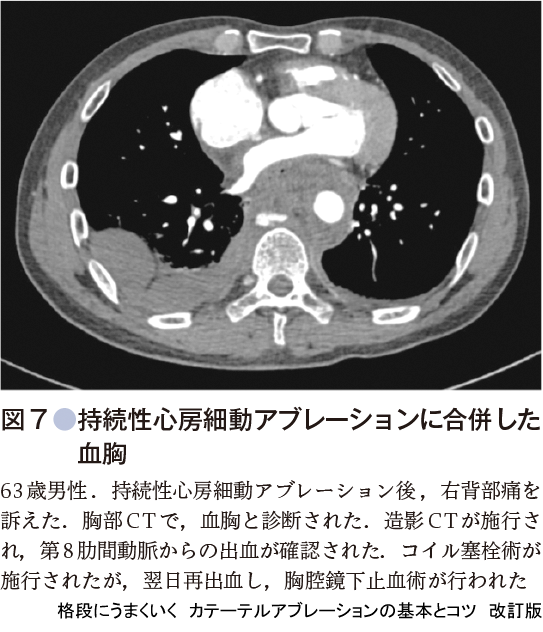

心房細動アブレーションに伴う血胸の合併率は,前述の世界規模の調査でも0.02%ときわめて稀である2).最近筆者らは(3施設)心房細動アブレーションに合併する血胸を3例(1症例/1施設)経験した.3施設合計の頻度は0.1%である.3例とも原因は第8肋間動脈の損傷であった.1例は死亡し,1例は肋間動脈コイル塞栓術を施行されたが,再出血し,胸腔鏡下止血術が行われ(図7),1例は開胸手術で止血術が施行された(図8).あとの2例は生存退院した.

図8の症例において,第8肋間動脈は左房の後壁を横切るように走行している(図9).特に右下肺静脈後壁は第8肋間動脈と近接しており,同部位でコンタクトフォースを強く,高エネルギーで通電すると,肋間動脈を損傷する危険性が高くなる.術前に肺静脈CTを実施する際に,肋間動脈も撮影すると,その近接の程度が明らかとなり,焼灼の際に注意できる.上記3例の経過より,仮に血胸を合併したら,すぐに開胸手術が望ましい.血胸の止血の遅れは死につながる可能性があるため,原因検索のための動脈造影も時間の無駄と思われる.血胸の原因のすべてが第8肋間動脈からの出血とは限らないが,開胸手術で原因検索と止血の両者が同時に可能である.また,早期発見のためには術中に右肺野も透視で確認する.血胸を合併すると肺野の透過性が低下しすぐに気がつく.